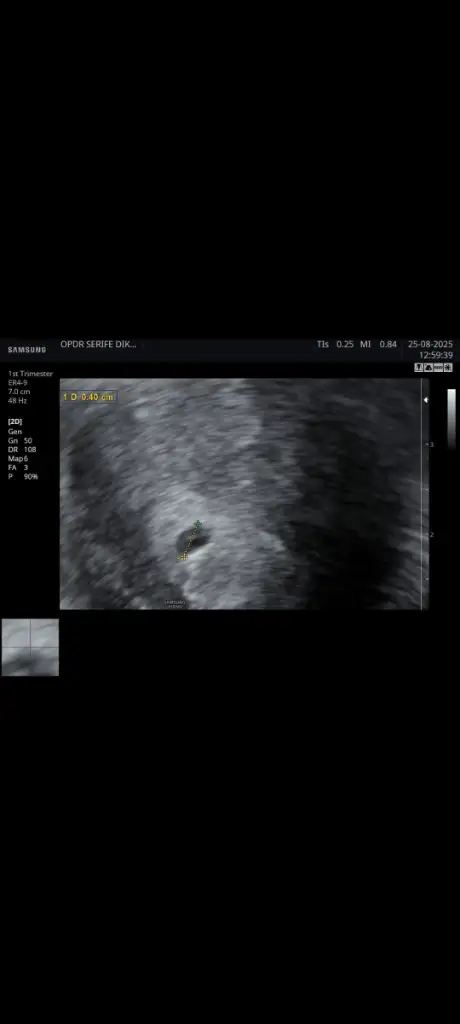

Hala kalp atışı yok ve kaç haftalık gebeyim onu bile bilmiyorum kalp atışı duyulmaması normalmi ultrason görüntüsüde ekliycem bilgisi olan varsa bana ne olduğunu anlatabilirmi